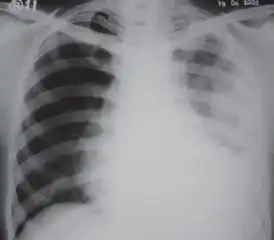

Extensive left-sided fibrothorax

Chest radiograph displaying inhomogeneous opacification of the left half of the chest that is fibrothorax